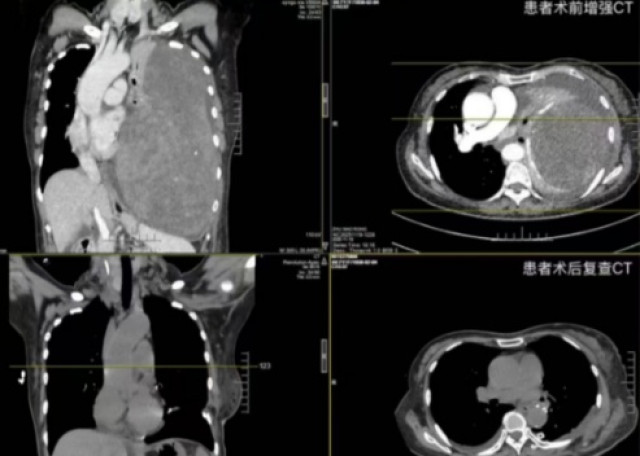

这一模式同样延伸至外科领域。湘雅医院日间手术中心优化术前评估、术中操作、术后康复全流程,推行“24小时入出院”服务,常规开展甲状腺肿瘤微创切除、肺癌胸腔镜及机器人手术等三四级高难手术。经过12年积累,该中心牵头制定了12个日间手术相关指南和专家共识,通过多学科协作,让有限的医疗资源服务更多患者。